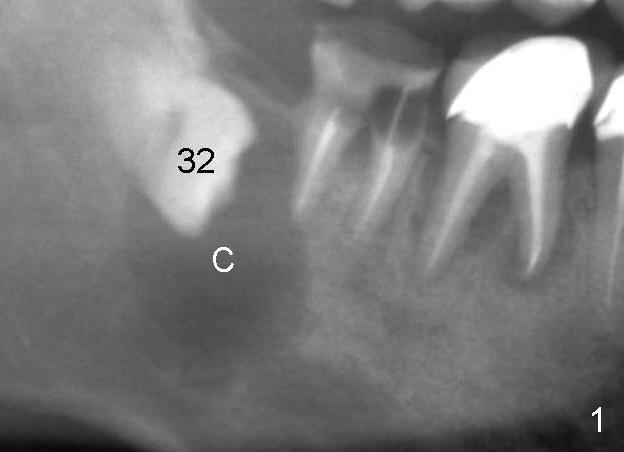

Immediately post extraction and cyst enucleation, osteotomy is formed in the mesial socket of the 2nd molar surrounded by intact bone (Fig.2 (T: 5x17 mm tap)).  Separation of the inferior alveolar neurovascular bundle from the cyst causes severe hemorrhage, which is stopped temporarily by gauze.